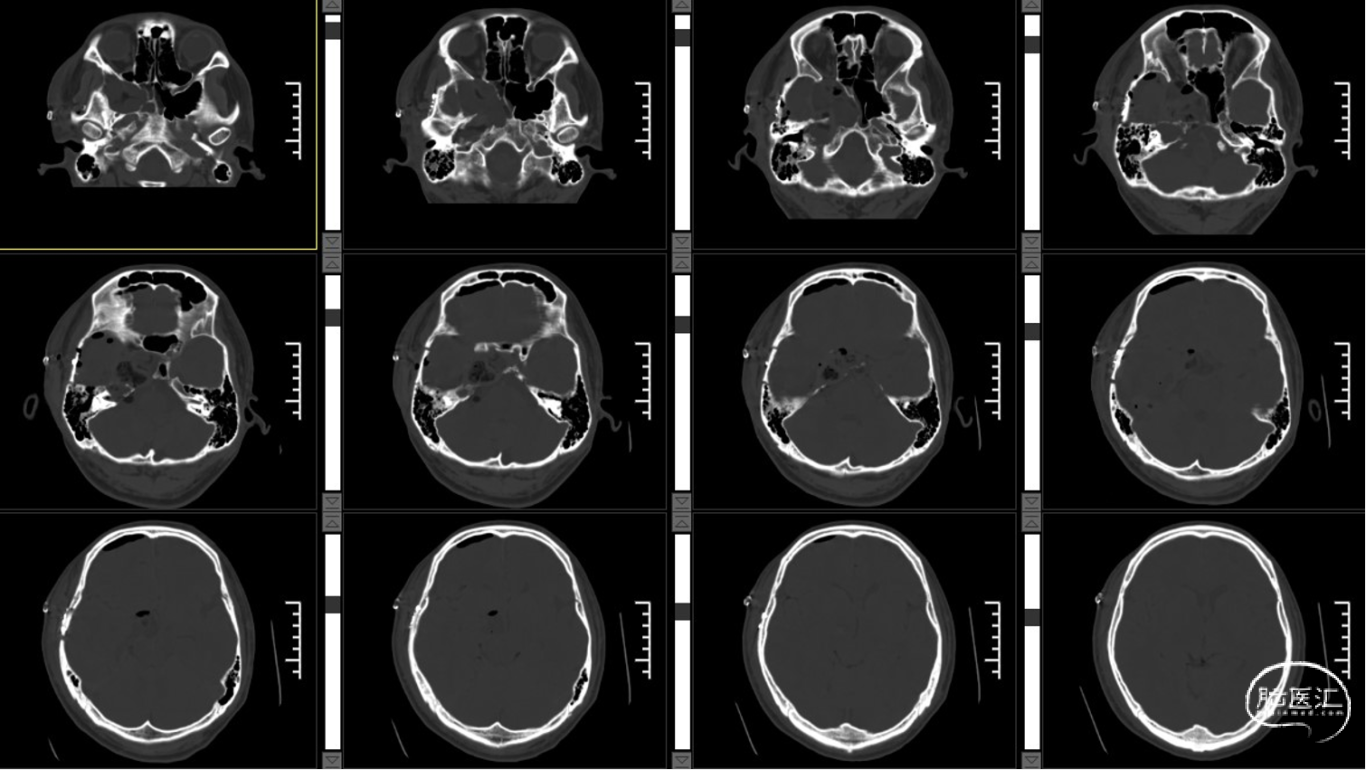

术后CT